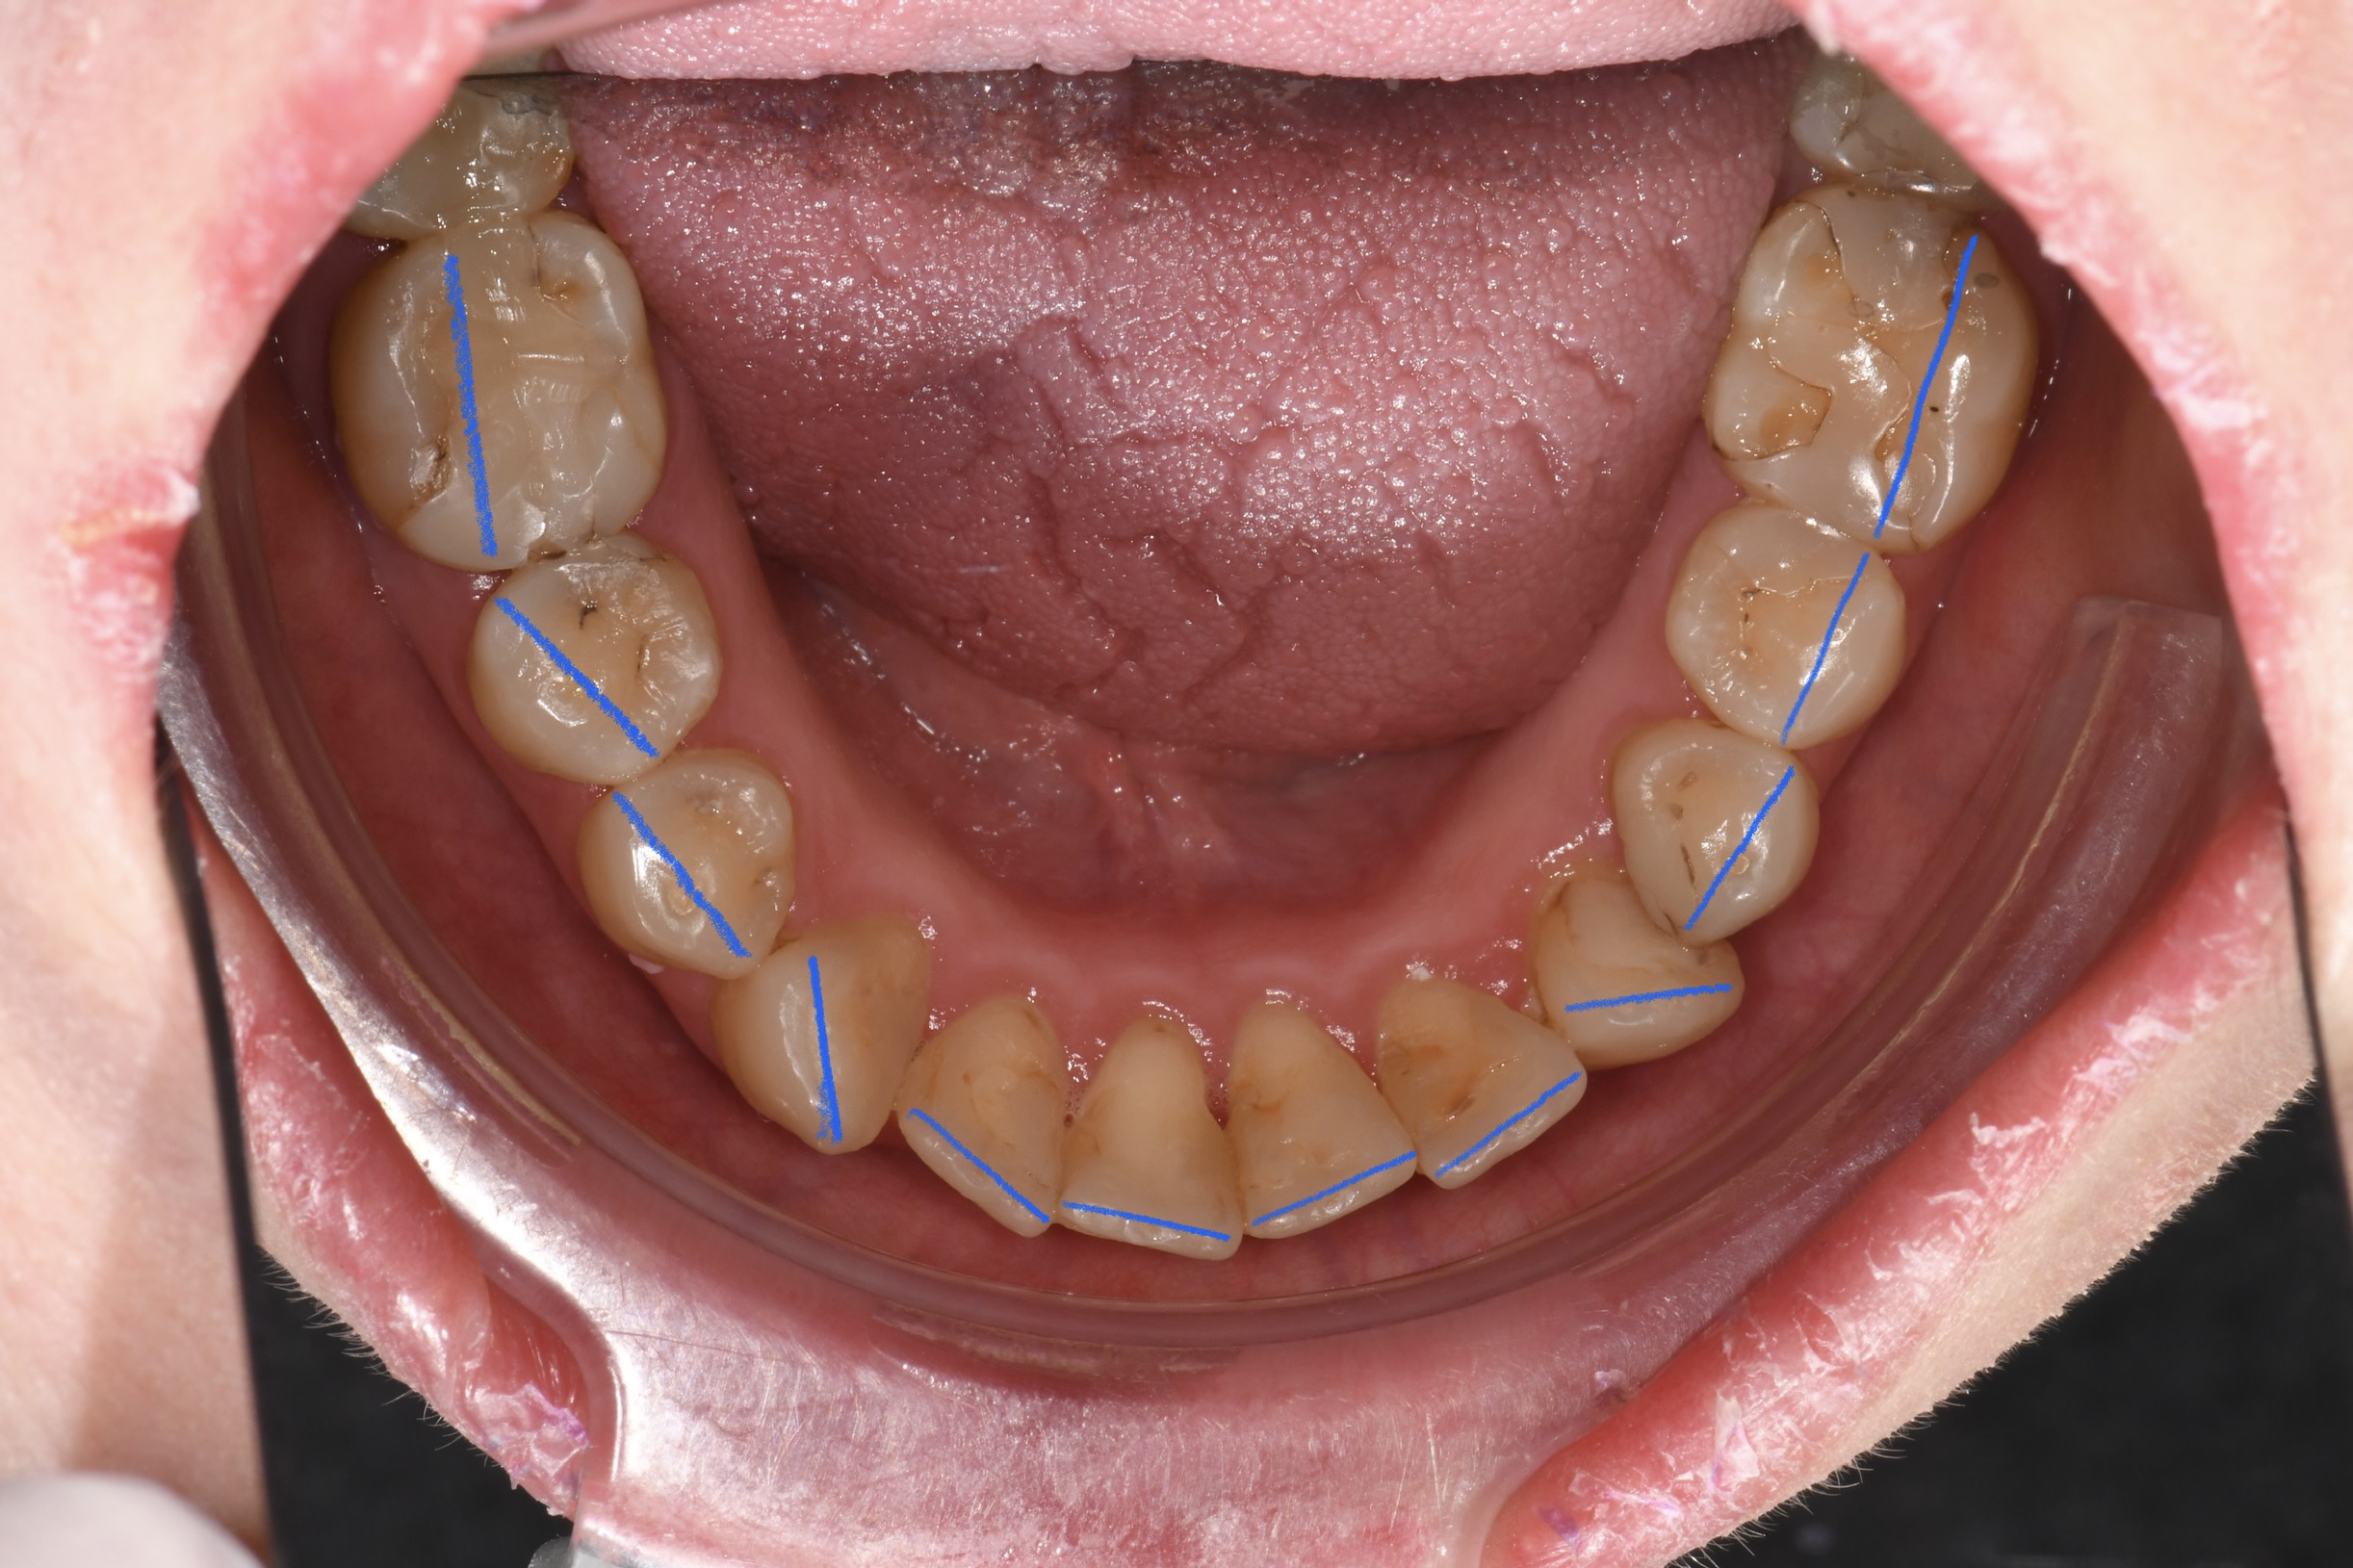

Az elmúlt évekből rengeteg szakmai referenciát tudnánk bemutatni, amelyek különböző fogszabályozási problémákat oldottak meg. Válogatva a több száz esetből, ezen az oldalon olyan képeket, információkat igyekeztünk bemutatni, amelyeknek a segítségével a jövőbeni pácienseinknek azt tudjuk üzenni: A Te fogsorod is lehet gyönyörű!

(Képeket a Pácienseink külön írásos beleegyezésével mutatjuk be!)